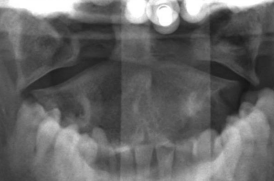

AP Open Mouth: Is this Image Good?

No.

Front incisors are superimposed over C1-C2

Atlantoaxial joint is not demoed

Excessive flexion of skull and neck

Reposition with slight extension of the neck or angle the CR slightly cephalic